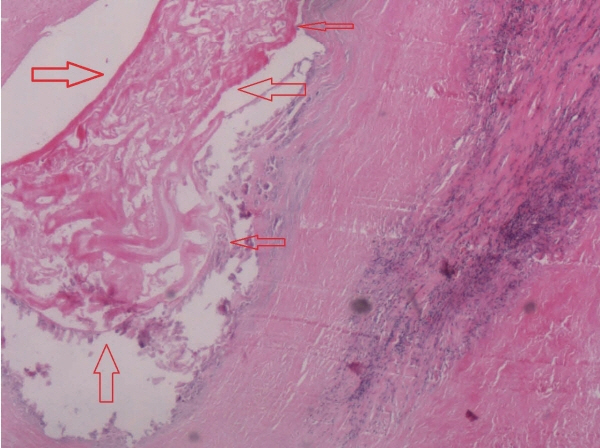

Fig. 4The pathological examination of surgical specimen manifested that alveolar cysts (the site indicated by the arrows) could be seen in bile duct epithelial tissues (H&E,×400).